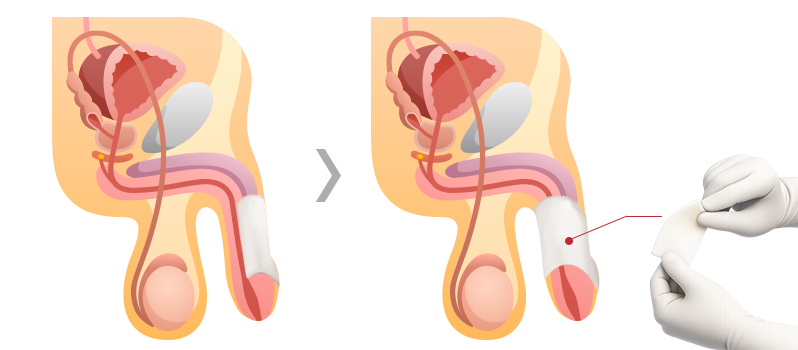

진피분말

유로진의 진피분말은 대체진피를

분말화하여 피부절개 없이

주사를 이용한 확대로

진피와 필러의 장점을 동시에 느껴볼 수 있습니다

특 - 징

- 피부절개가 없는 비수술 확대

- 10여분 정도의 짧은 시술 진행

- 진피를 분말화한 재료로 긴 확대 지속기간

필 러

유로진은 액상형태인 필러 특성상 시술시 형태가

매우 중요하므로

상·중·하 피하층에 골고루

동시 주입하여 자연스러움과 확대효과를 높입니다

특 - 징

- 피부절개가 없는 비수술 확대

- 10여분 정도의 짧은 시술 진행

- 흉터 및 회복기간에 대한 부담이 거의 없음

자가지방

유로진은 지방 속 수분·혈액을 걸러주는

압축·정제과정을 통해

순수지방만을

사용하여 확대 지속효과를 높였습니다